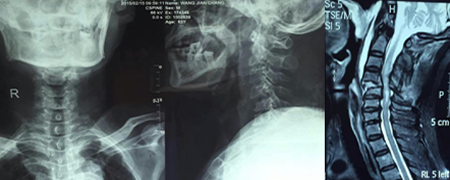

頸椎骨折并脊髓損傷前后路聯(lián)合椎管減壓植骨融合內(nèi)固定術(shù)